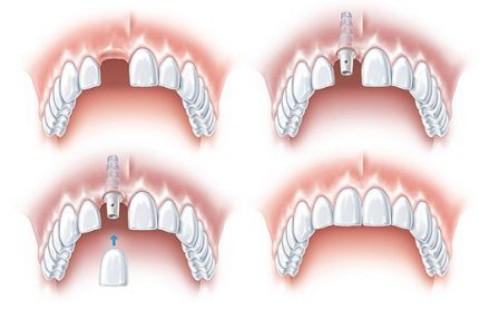

Trồng răng cố định bằng implant cho 1 răng cửa

Đây được cho là phương án phục hình tối ưu nhất vì có thể khôi phục chân răng bị mất bằng một trụ implant. Khi có implant trong xương hàm thì phần xương khu vực đó sẽ không bị tiêu đi và chức năng an nhai cũng được phục hồi tốt nhất. Với phương án này, các răng bên cạnh không bị ảnh hưởng gì. Chi phí implant hiện tại khoảng 20 - 30 triệu/ răng tùy vào thương hiệu implant. Thời gian trung bình khoảng 1 tuần đến 6 tháng tùy vào từng trường hợp cụ thể.